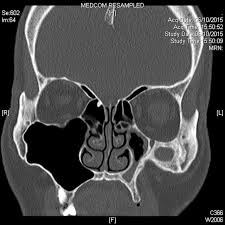

Silent Sinus Syndrome Ct And Mri Findings Bmj Case Reports

Pdf Silent Sinus Syndrome Ct And Mri Findings